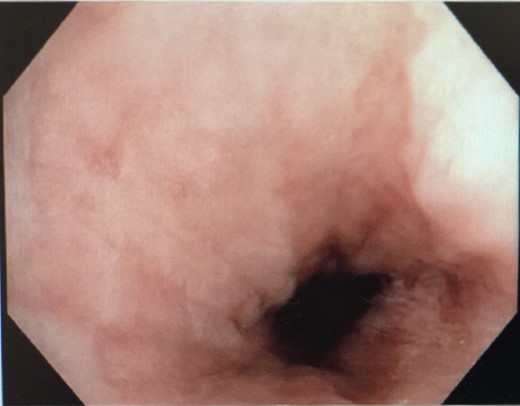

He was kept nil orally. Analgesia, antiemetics, IV proton pump inhibitor, and empirical IV antibiotics were commenced. Esophagastroscopy showed large hiatus hernia with reflux esophagitis. Middle-lower third esophagus appeared patchy, gangrenous from 27 cm to gastroesophageal-junction at 35 cm (Fig. 2). Multiple biopsies for viral culture and microbiology showed chronically inflamed cell infiltrates consistent with mucosal ischemia. No viral inclusions are seen. At the end of procedure, a PEG with jejunal extension tube was inserted to commence feeds.